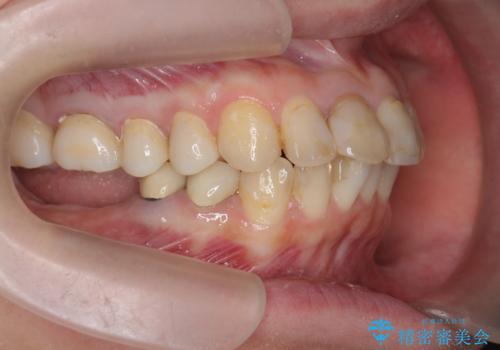

インプラント・セラミック・矯正治療を含む包括歯科診療

- 「地元の歯医者にずっと通っているが、どんどん歯が悪くなる。時間とお金がかかってもいいので徹底的に歯を治したい。」

、と総合的な歯科治療を希望されて来院されました。

虫歯や咬合関係・歯槽骨の吸収・根尖病変・歯の欠損・複合的な問題を一つずつ解決し、

安定した噛み合わせの構築・歯ブラシのしやすい環境の整備・歯内歯周の感染除去・造骨を伴うインプラント治療

を行い、長期的な予後を見込める口腔内環境を確立、整備して行きます。